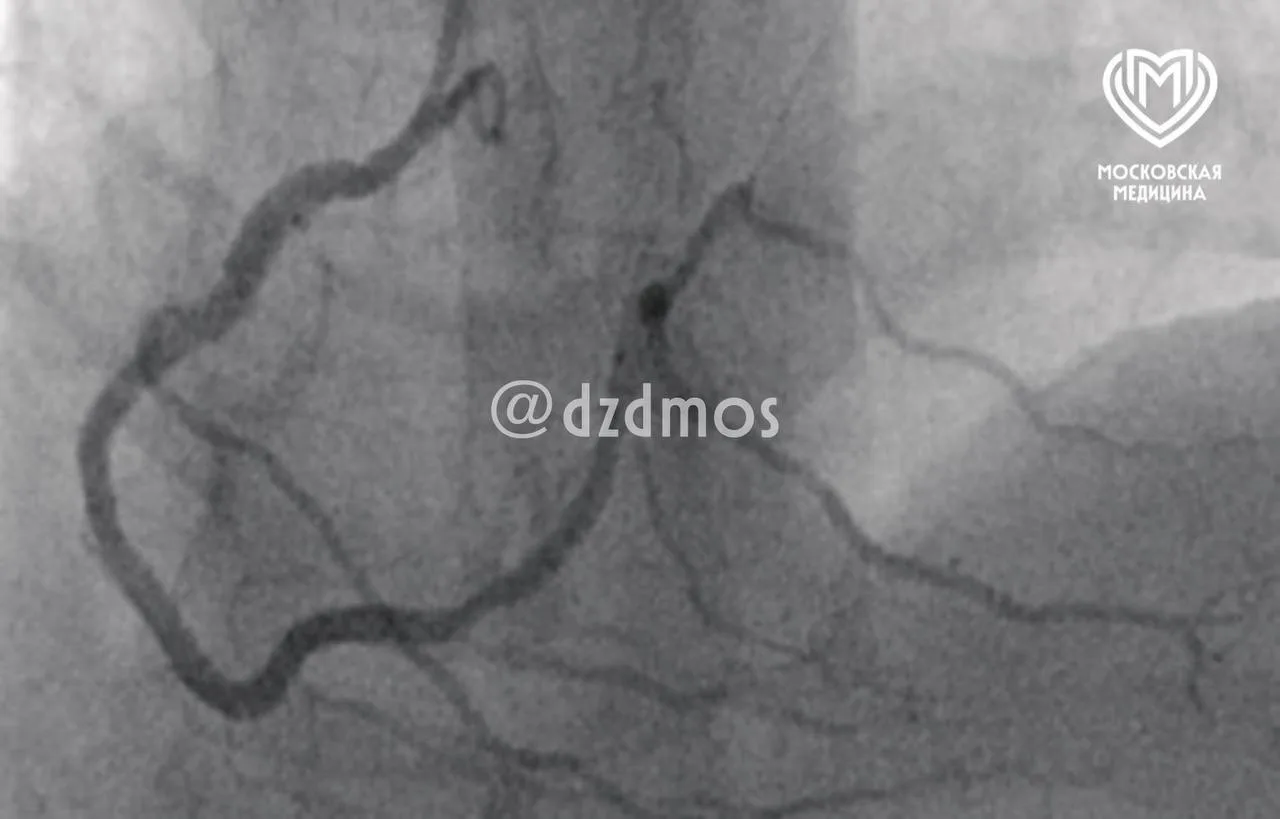

🤯 Инфаркт из-за куска мяса

Москвич съел свинину и столкнулся с редком синдромом Коуниса, когда аллергическая реакция приводит к опасным нарушениям в работе сердца.

К счастью, профессионалы из скорой помощи и и ГКБ №15 спасли пациента. Он уже дома и теперь вряд ли будет экспериментировать с рационом…

Ну а столичным врачам — в очередной раз наши аплодисменты 👏

📸 Депздрав Москвы